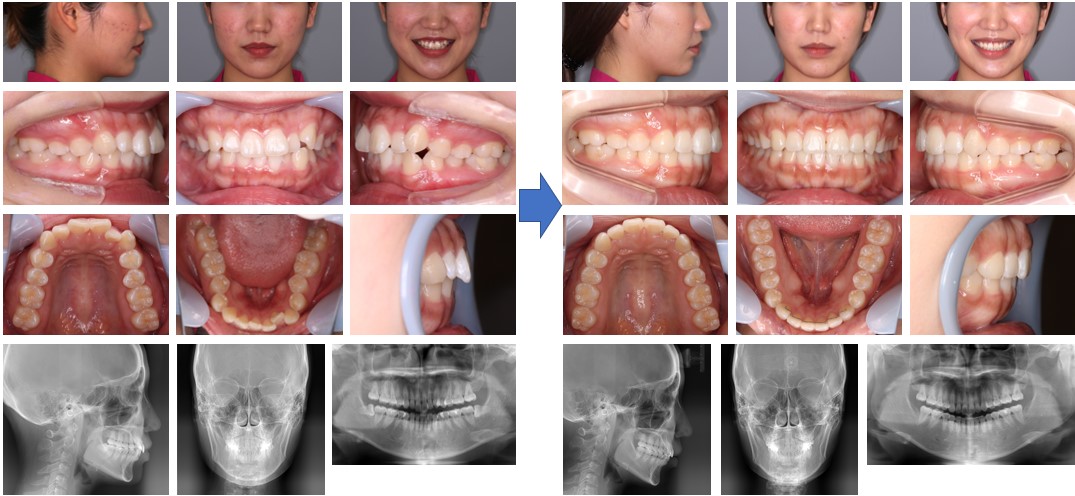

【治療例】初診時年齢:23歳4か月 / 性別:女性 / 主訴:上の歯が出てきた気がする、正中がずれている

症例の概要:この症例は、当院で幼少期にマルチブラケット装置にて治療を行ったが、成人になって上の前歯が出てきた気がするということで来院された。下顎の正中が顔面正中に対して左方偏位していることで左側の臼歯関係はⅡ級を呈した。マウスピース型(アライナー型)矯正装置(インビザライン®)でIPRを行いながら唇側傾斜の改善ならびに正中線の一致を試みた。その結果、左側の臼歯関係はⅠ級関係を築き、唇側傾斜の改善および正中線が一致した。

主訴:上の歯が出てきた気がする、正中がずれている

診断名: 左側アングルⅡ級の上顎前突症例

使用した主な装置: マウスピース型(アライナー型)矯正装置(インビザライン®)、IPR、顎間ゴム

抜歯/非抜歯および抜歯部位: 非抜歯

※こちらの症例は2023年5月から2024年12月に行った矯正歯科治療です(現在も経過観察中)

治療期間:1年7か月

治療回数:19回

リスクの副作用:歯の移動や抜歯による違和感や疼痛、口内炎、歯肉退縮、歯根吸収が生じることがある